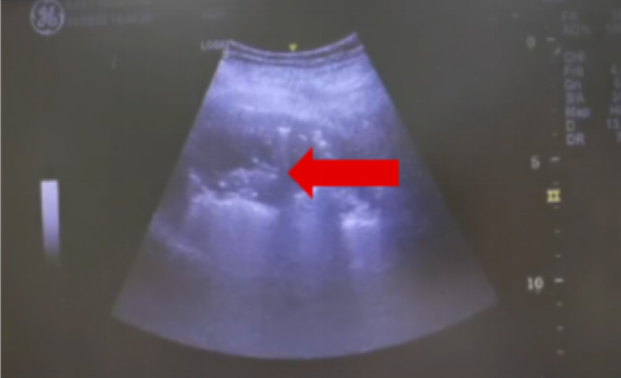

图片

图3  经胸壁超声引导下TBCB(红色箭头为冷冻探头)